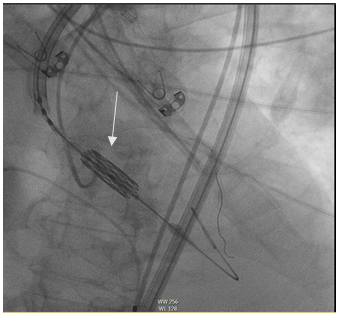

In the previous study, it appeared that the origin of the left common trunk could be compromised by the TAVI stent, so it was decided to perform left coronary protection with a 3.5 (6F) EBU catheter, Asahi Sion angioplasty guidewire and NC angioplasty balloon through the right brachial artery.

Percutaneous therapeutic access through the right femoral artery, successful implantation of Sapien 3 valve, nº26 (Edwards) (Figure 7 and 8).

Figure 7 Alignment of valve prosthesis.